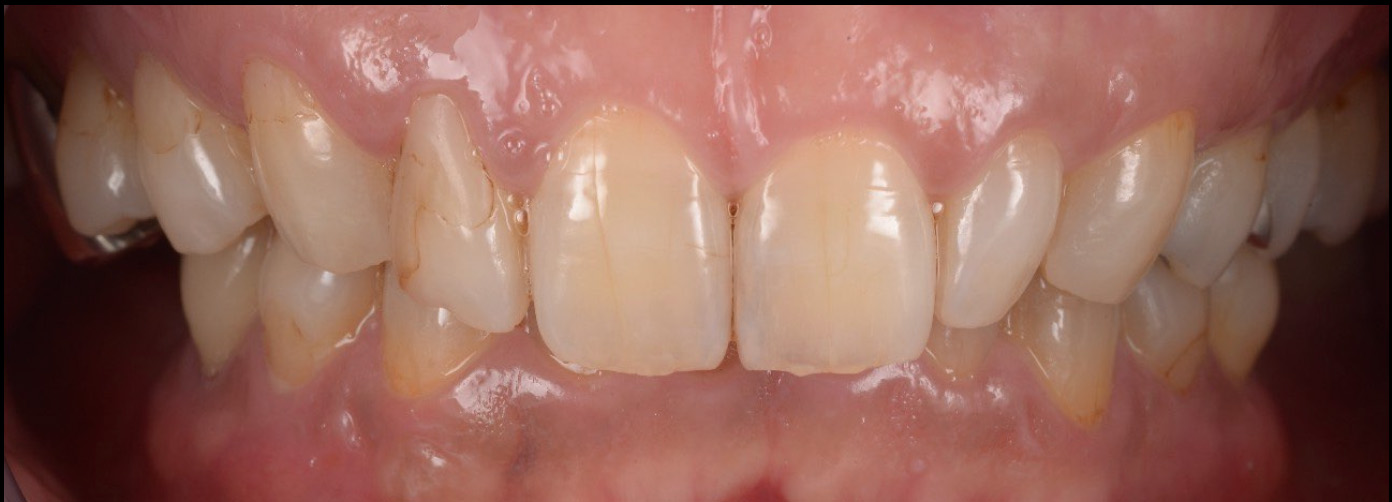

治療前